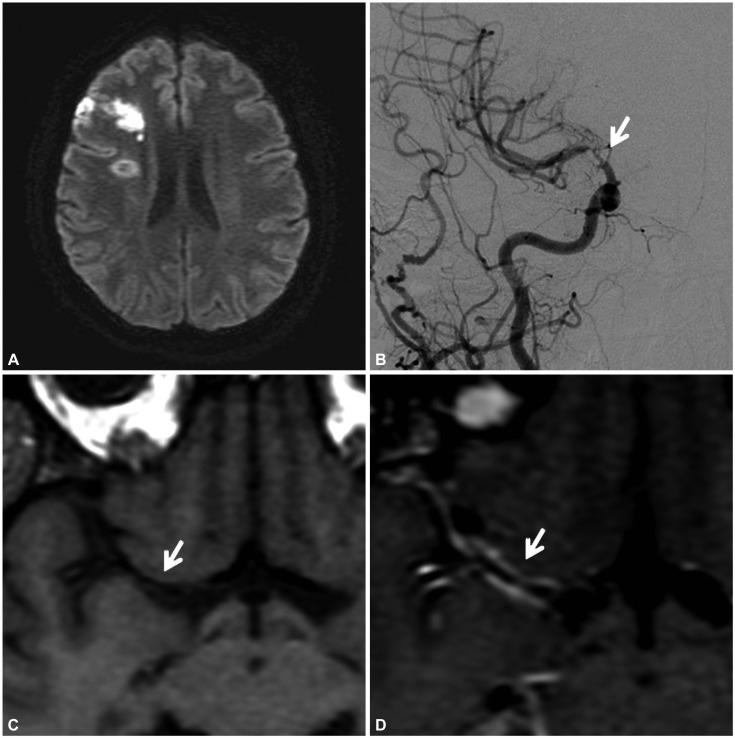

Cerebral Large-Vessel Vasculitis in Sjogren's Syndrome: Utility of High-Resolution Magnetic Resonance Vessel Wall Imaging.

J Clin Neurol. 2018 Oct;14(4):588-590. doi: 10.3988/jcn.2018.14.4.588.